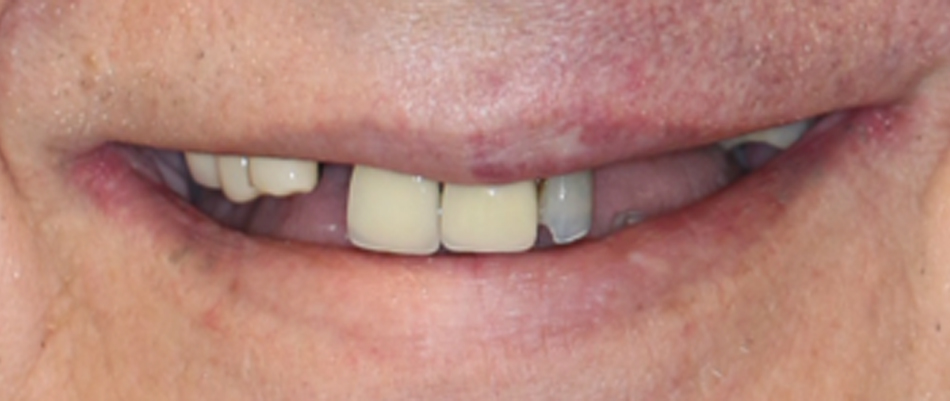

Patient 4 - Before

Pre-treatment patient presentation